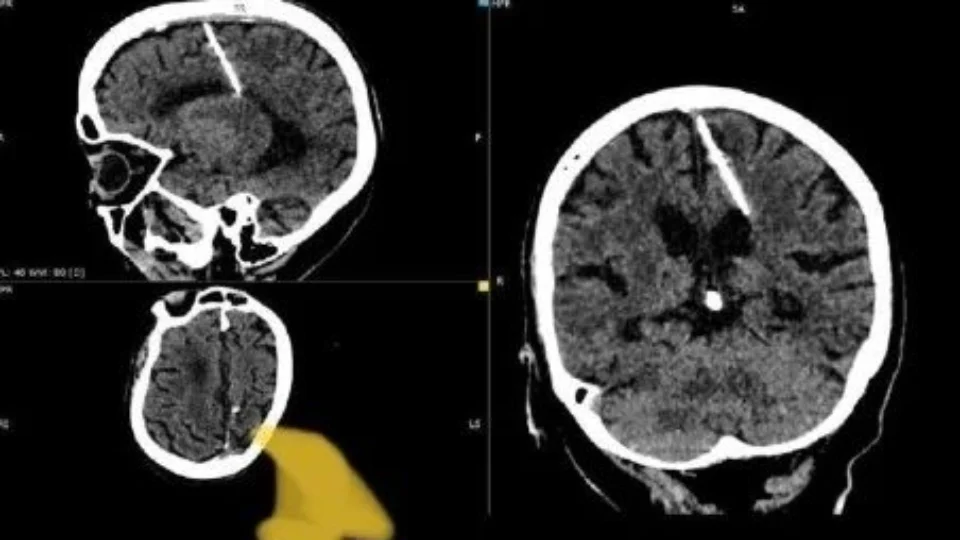

Após 80 anos, idosa descobriu que tinha uma agulha de 3 centímetros cravada no cérebro desde a infância, vítima de uma tentativa de infanticídio.

Uma idosa, de 80 anos, descobriu que convivia há décadas com uma agulha de 3 centímetros no cérebro.

O caso foi descoberto durante um exame de tomografia realizado por médicos na Rússia.

Os profissionais cogitam que a agulha, encontrada na cabeça da idosa, está com ela desde a infância.

Com o desenvolvimento da ‘moleira’ da criança, os ossos da cabeça foram se formado, deixando a agulha presa.